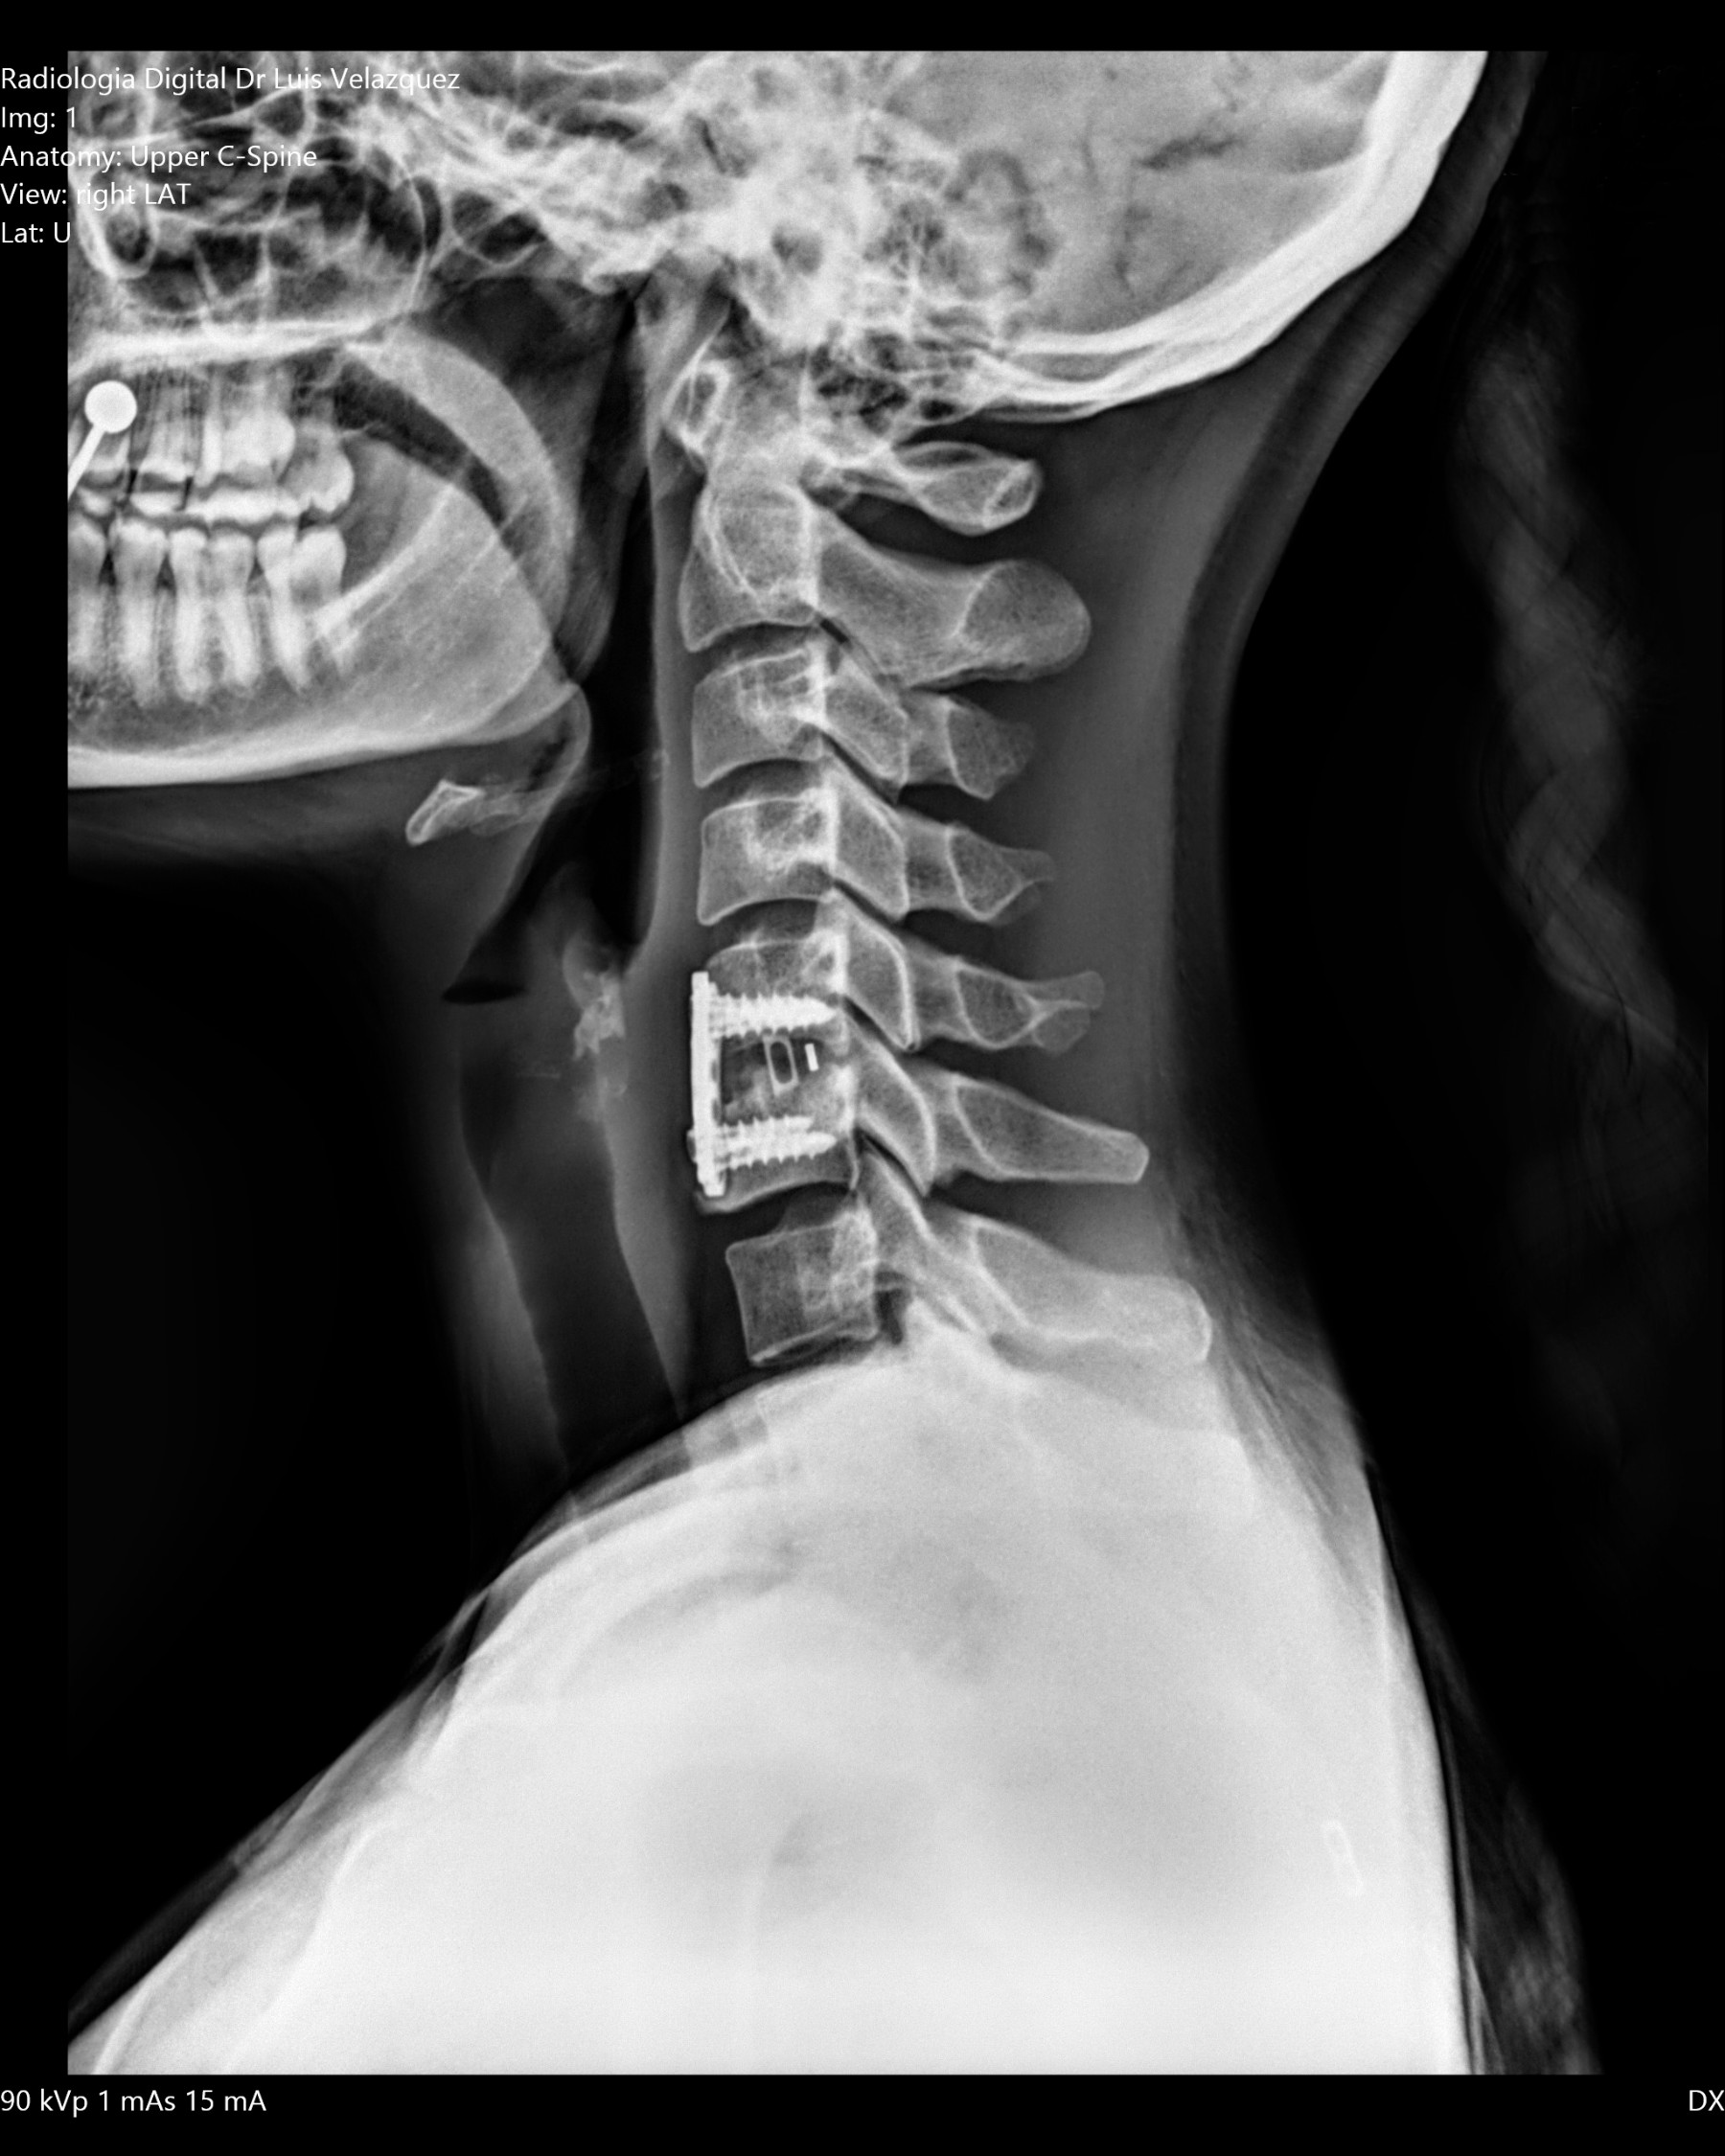

Radiología Digital como Herramienta Complementaria en el Dictamen de Bienes Muebles

Desde el descubrimiento de los rayos “X” y las placas radiográficas por Wilhelm Conrad Roentgen y su posterior difusión a través de la Asociación Físico médica de Wurzburg el 28 de diciembre de 1895, que fue la primera asociación que habló de los nuevos rayos que podían penetrar el cuerpo y fotografiar los huesos, ha habido muchos cambios tanto en la forma de obtener, procesar e incluso en la forma de visualizar, manejar y almacenar las placas radiográficas.